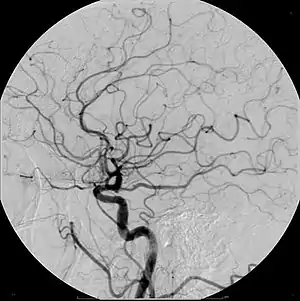

Example of iodine based contrast in cerebral angiography

Iodinated contrast contains iodine. It is the main type of radiocontrast used for intravenous administration. Iodine has a particular advantage as a contrast agent for radiography because its innermost electron ("k-shell") binding energy is 33.2 keV, similar to the average energy of x-rays used in diagnostic radiography. When the incident x-ray energy is closer to the k-edge of the atom it encounters, photoelectric absorption is more likely to occur. Its uses include: